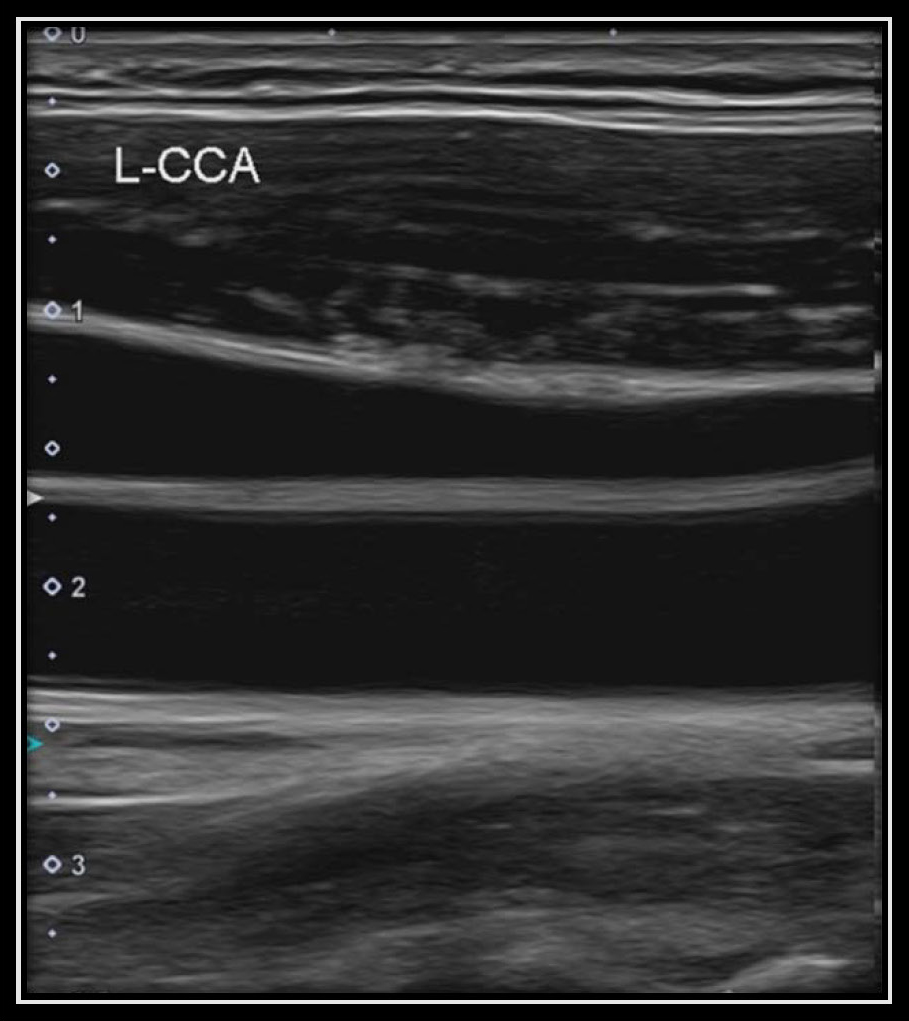

頸動脈エコー検査での1例

頸動脈エコー検査とは、動脈硬化の進行具合を調べることが可能な検査です。

【正常な血管】

血管にプラーク(コレステロールの塊)などがなく、詰まりがない状態